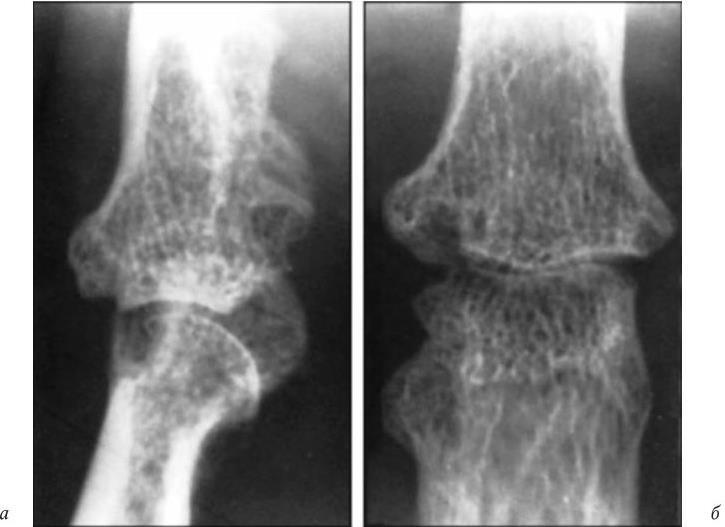

Рис. 15. Рентгенограмма коленных суставов больной со II стадией РА:

а — головка большеберцовой кости имеет ровные округлые контуры; б — в коленном суставе видна четкая краевая деструкция, узурация эпифиза большеберцовой кости

Рис. 16. Рентгенограмма пястно-фалангового сустава больной РА, III стадия, 6-кратное увеличение рентгеновского изображения

Глубокие краевые дефекты костной ткани, деструкция костной ткани в головке и основании пястно-фалангового сустава (а — боковая проекция; б — прямая проекция)